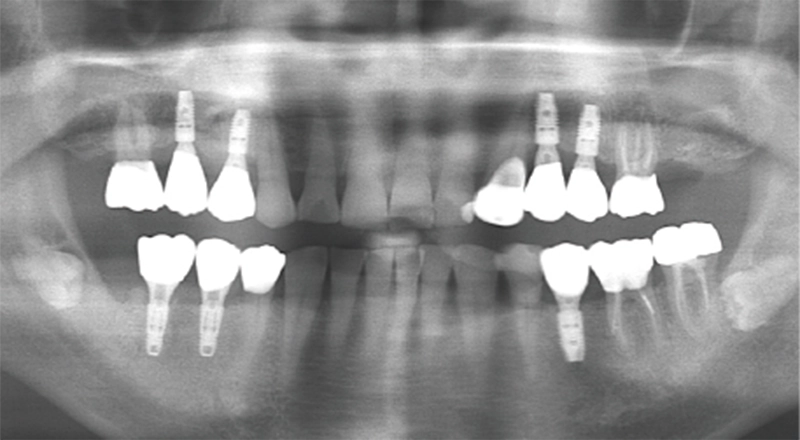

| 主訴 | 歯が抜けている。 入れ歯のところをインプラントしたい |

|---|---|

| 診断名 | 歯の欠損、義歯不適合 |

| 年齢・性別 | 63歳・男性 |

| 治療期間・回数 | 1年3ヶ月・33回 |

| 治療方法 | 精密根管治療、ジルコニアクラウン、GBR、インプラント、ホワイトニング |

| 費用 | 3,949,000円 最高プラン (費用を抑えたプランも提案可能) |

| 治療上のリスク |